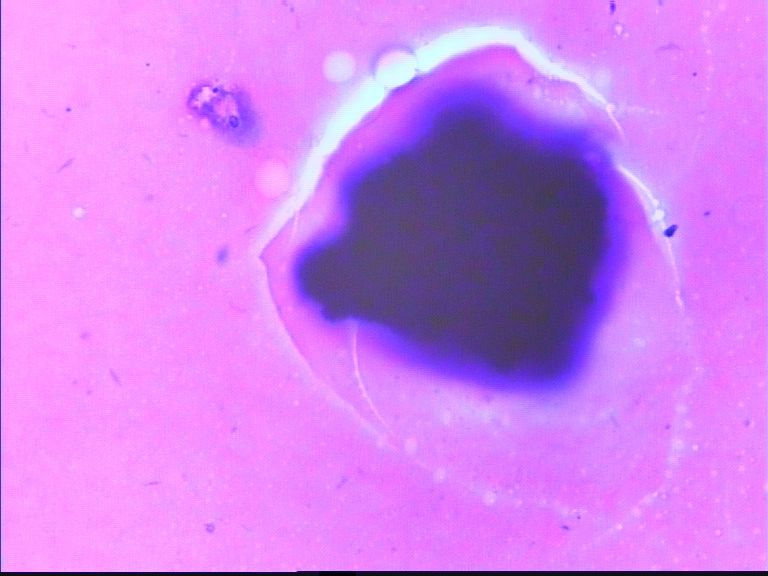

67岁胸水,有风湿病

• 67岁胸水,有风湿病图2

图2

没看出有设么异常细胞   图20好像有霉菌菌丝

如果怀疑深染的东西里有细胞,那就加热加盖片的位置,取去盖玻片,在二甲苯里溶去封固胶,从高浓度到低浓度的酒精去掉二甲苯,直至水洗,再进入盐酸酒精里,再分化一会儿,看颜色退去些后,能不能看见有细胞结构。目前确实什么都看不见,也说不了什么。

深的可能是染料渣子

深染的东西像杂质

这些深染的是什么东西呢?好奇怪

制片质量欠佳,直接就看不出是什么了!

看不清,不能诊断

深染的不是细胞(就是细胞,看不到结构,也不能诊断)。